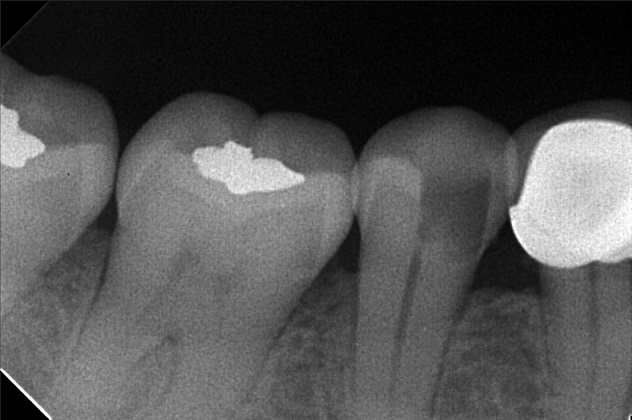

- Procedure

- File 3

- sevilla_03.jpg